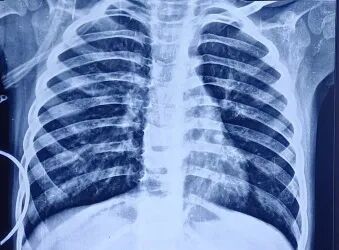

胸片显示双肺野过度充气,伴右肺中野不均匀浸润影及支气管壁增厚(图1)。胸部高分辨率CT扫描显示右肺上叶前段可见厚壁囊腔,可能存在交通,紧邻管壁明显增厚的亚段支气管——提示囊性支气管扩张(图2)。免疫功能缺陷检查已排除:HIV报告正常,免疫球蛋白谱正常,淋巴细胞亚群分析正常。IgA=54.67 mg/dL,IgG=990.32 mg/dL,IgM=404.186 mg/dL,IgE=16.3 IU/mL,CD3(T细胞)=2237.32 个/μL ,62.85% ;CD4 TH细胞=1165.21 个/μL ,32.73% ;CD8 T细胞=1065.26 个/μL,29.92%;CD4/CD8比值1.09均处于正常范围

1.患者入院时胸片显示双肺野过度充气,左肺中野不均匀密度增高影伴支气管周围增厚。